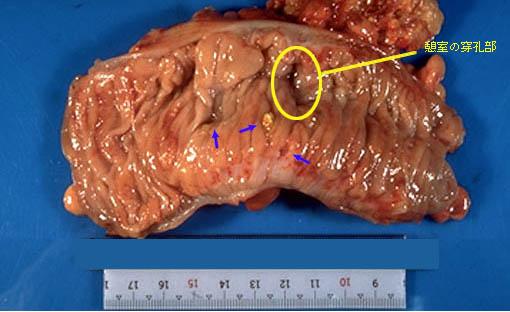

疾患(病理主体)の分類憩室/憩室炎・憩室周囲膿瘍

部位(臓器別)大腸/S状

検査方法マクロ

病変の最大径(ミリ)40以上